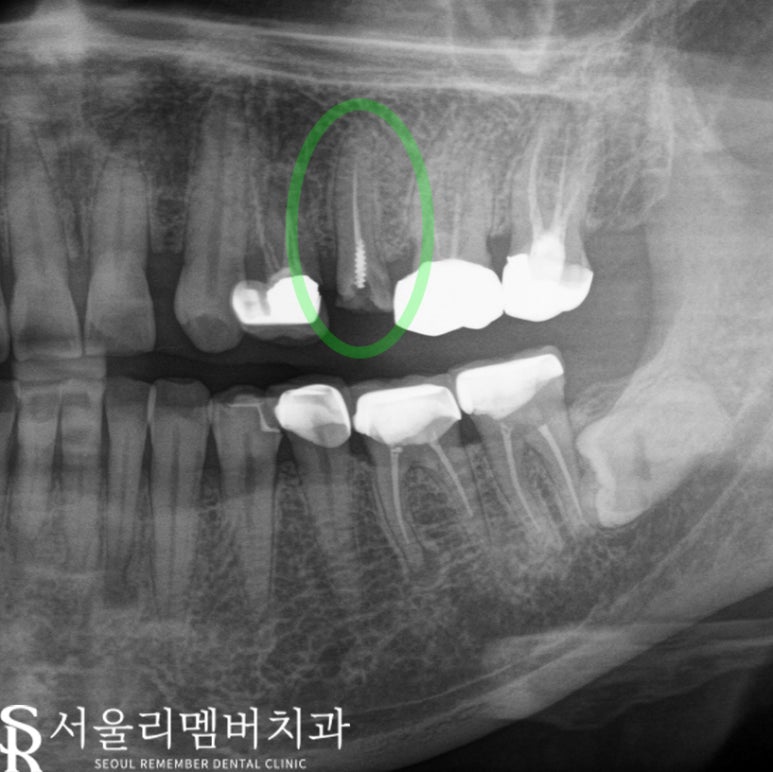

✅ #14와 #25

사당 치과 는 발치 후 바로 임플란트를 진행했습니다.

이 과정에서는 Navigation Implant를

사용해 높은 정확도와 빠른 회복을

기대할 수 있었습니다.

발치 후 즉시 식립을 통해 즉각적인 기능

회복과 빠른 회복 시간을 기대할 수 있었습니다.

또한, Navigation Implant를 사용하면

정확한 위치에 임플란트를 식립할 수 있어

수술 후 통증과 부기를 최소할 수 있는 점이 있죠.

이제, 식립 후 몇 개월의 시간이 지나면

최종 보철 단계로 넘어가게 됩니다.

✅ #17, #14, #25 최종 보철

임플란트 식립 후 약 2개월이 지나

무사히 식립이 완료되었고,

#17과 함께 #14와 #25에

최종 보철을 완료했습니다.

이로써 환자께서는 통증 없이

생활하실 수 있게 되었습니다.

최종 보철은 자연스러운 외관과 함께

기능적인 측면에서도 중요 역할을 수행하죠.